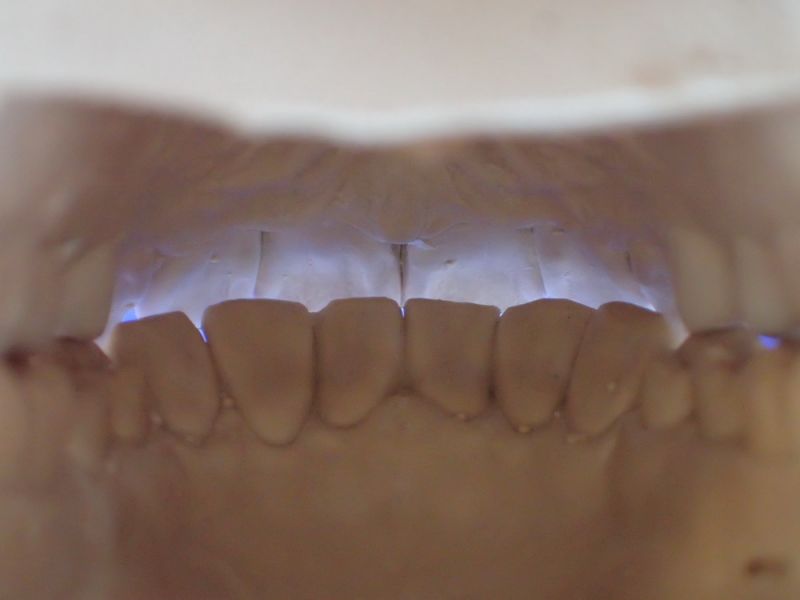

Mann kann hier sehr gut an den beiden Punkten der distalen Dreipunktabstützung erkennen, mit welch hoher Passgenauigkeit die Zentrikplatten auf die Gipszähne der Meistermodelle aufgebacht werden können und müssen.

Es ist einer dieser Detailpunkte, der darüber entscheidet, mit welcher Anfangspassgenauigkeit ein 'A'ufbissbehelf am Ende eines langwierigen Arbeitsprozesses in der Mundhöhle des Patienten eingeglidert werden kann.